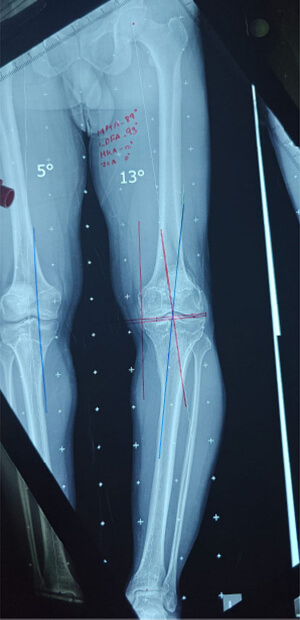

DEFORMITY CORRECTION